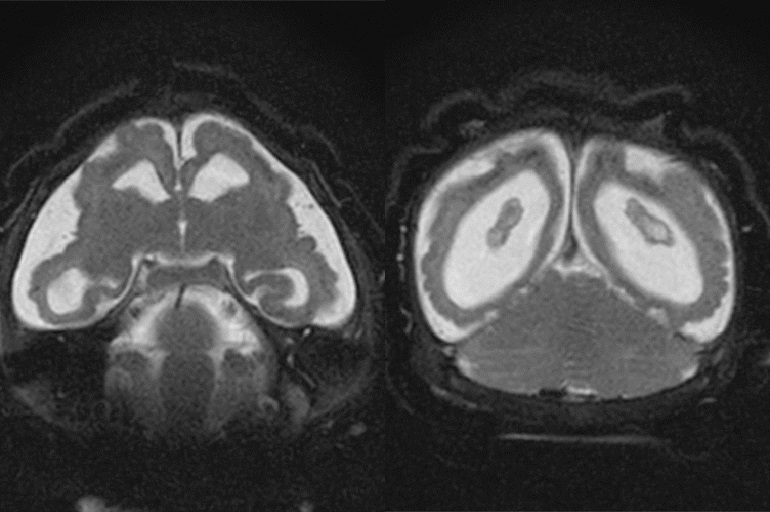

The development: Scientists in Brazil reported last week on an infant, whose mother contracted the virus late in pregnancy, which has typically been considered a less vulnerable time. The infant didn’t show signs of developmental problems but still had Zika in his urine, saliva and serum two months after being born. By six months, the child had begun showing signs of brain impairment — suggesting the virus can linger longer in babies’ systems and cause health problems later than previously believed.

In a clinical guidance published before the Brazil report, the Centers for Disease Control and Prevention called for regular assessments of children who may have been exposed in utero. Practically, that means tracking things like head size and how babies progress in terms of vision and hearing responses as well as their ability to feed.

“Once the baby is born, [we need to] have them be monitored and followed, even if there’s no microcephaly,” said Peter Hotez, dean of the National School of Tropical Medicine at Baylor College of Medicine in Houston, and an expert on the virus.